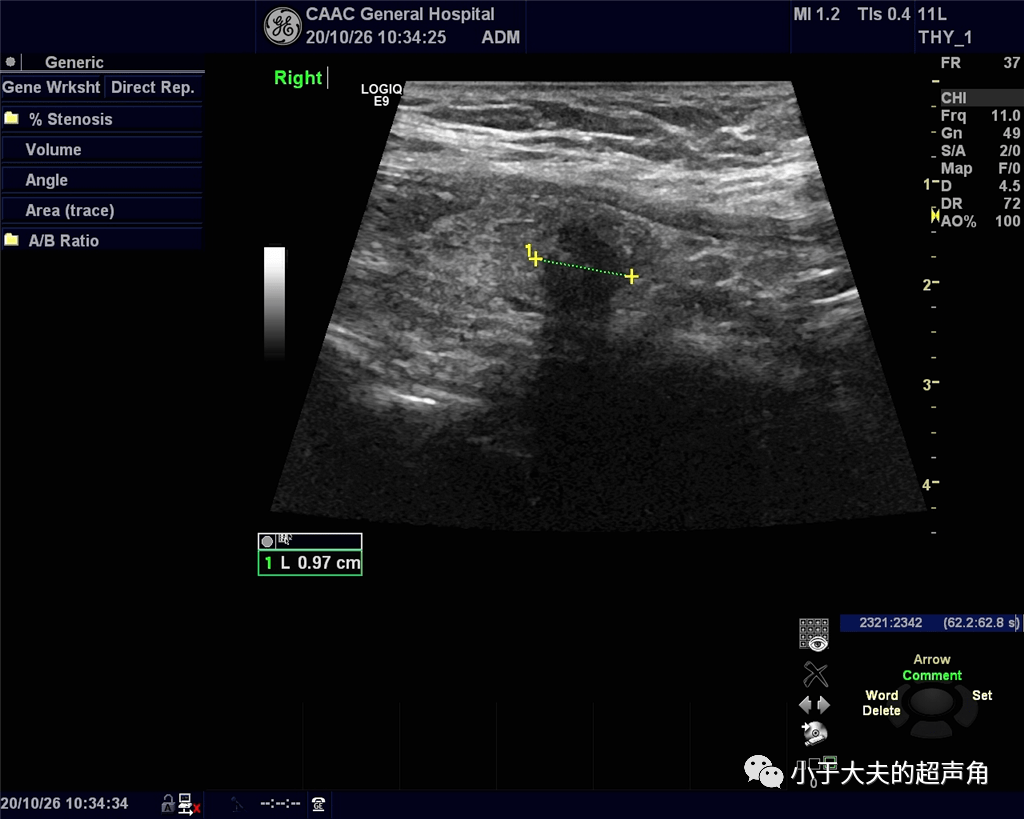

再问:『这甲状腺结节会是坏家伙吗?』_超声_钙化_伴声

图片尺寸1024x819